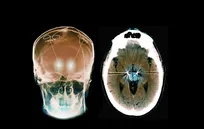

ایمپلنت مغزی شخصی‌سازی شده، نجات‌بخش زن مبتلا به وسواس شدید

دستگاهی در مغز یک زن مبتلا به اختلال وسواس فکری-عملی (OCD) و صرع، با تشخیص الگو‌های غیرطبیعی فعالیت عصبی و ارسال ضربان‌های الکتریکی در لحظه مناسب، توانست دو بیماری شدید را همزمان کنترل کند.